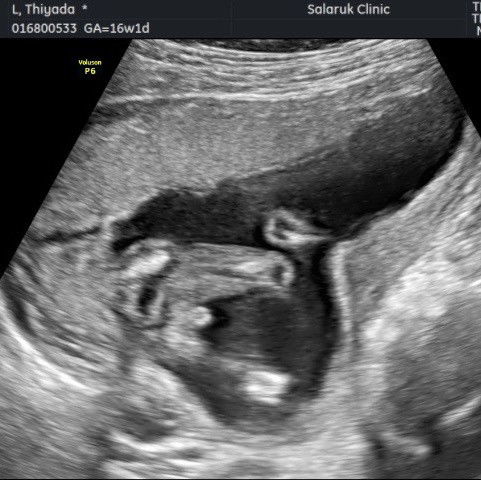

แม่ๆว่ามีจูจู้ มั้ยคะ

ที่บ้านมีแต่คนอยากได้ลูกสาว แต่ซาวเมื่อวานคุณบอกบอกว่าอาจจะเป็นผู้ชายหรือไม่ก็สายสะดือ

เราก็แบบนี้ค่ะแม่ตอนแรกก็อาจจะคิดว่าเป็นสายสะดือสรุปไม่ใช่สายสะดือ สรุปก็ปุ๊กกู๋น้อยนั้นแหละ555

เหมือนจะมีค่าแม่